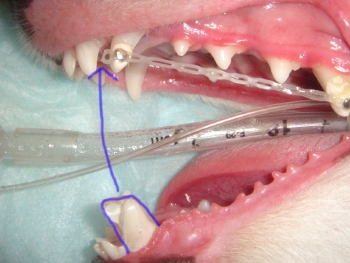

クロスバイトとは、前歯の一部は正常なかみ合わせであり、一部は下顎が上顎より前に出ていて(出っ歯)の状態をいいます。つまり上下の歯列のどこかで交叉しているかみ合わせのことをいいます。放置したり、「ひっぱりこ」の遊びをすることで、クロスバイトは悪化し、下顎の前歯が外にでるようになってしまします。今回はクロスバイトの矯正としてアクリル板およびリンガルボタンを使用した方法をご説明いたします。

初診時での写真です。下顎の前歯が上顎の前歯より飛び出ています。

切歯の一番右端を斜め後方(捻りながら喉側)に牽引し、隣の切歯が喉側に牽引されるスペースを作ります。その際、矯正モデルにより、上顎の切歯が移動されないよう十分に注意した模型の作製および設置を心がけます。

印象作成後、アクリルにて矯正器具を設置いたしました。この場合は、犬歯をアンカーとして使用し、前歯が後ろに牽引される際、他の歯が動かないようにします。

力の加減、大きさを間違えますと、歯が弱くなったり、上顎の前歯全体に支障を来し、歯の形態が崩れます。

矯正2ヶ月。下顎の前歯が正常の位置に戻っております。